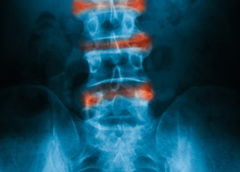

Osteoartrosi, il circolo vizioso che rovina la cartilagine

Uno sfortunato ciclo biologico spinge le cellule della cartilagine in un’articolazione artrosica a contribuire alla progressione della malattia, secondo quanto dimostrato in un recente studio. Le cellule che costruiscono e mantengono la cartilagine sono chiamate condrociti, e sulla loro superficie si possono trovare canali…